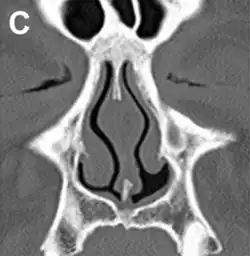

.jpg)

It has been proposed, that the airflow in ENS is changed so that most of the air flows through the middle meatus, compared to most of the air flowing through the inferior meatus in healthy individuals. This can be corrected via inferior meatus augmentation (IMAP surgery).[25]